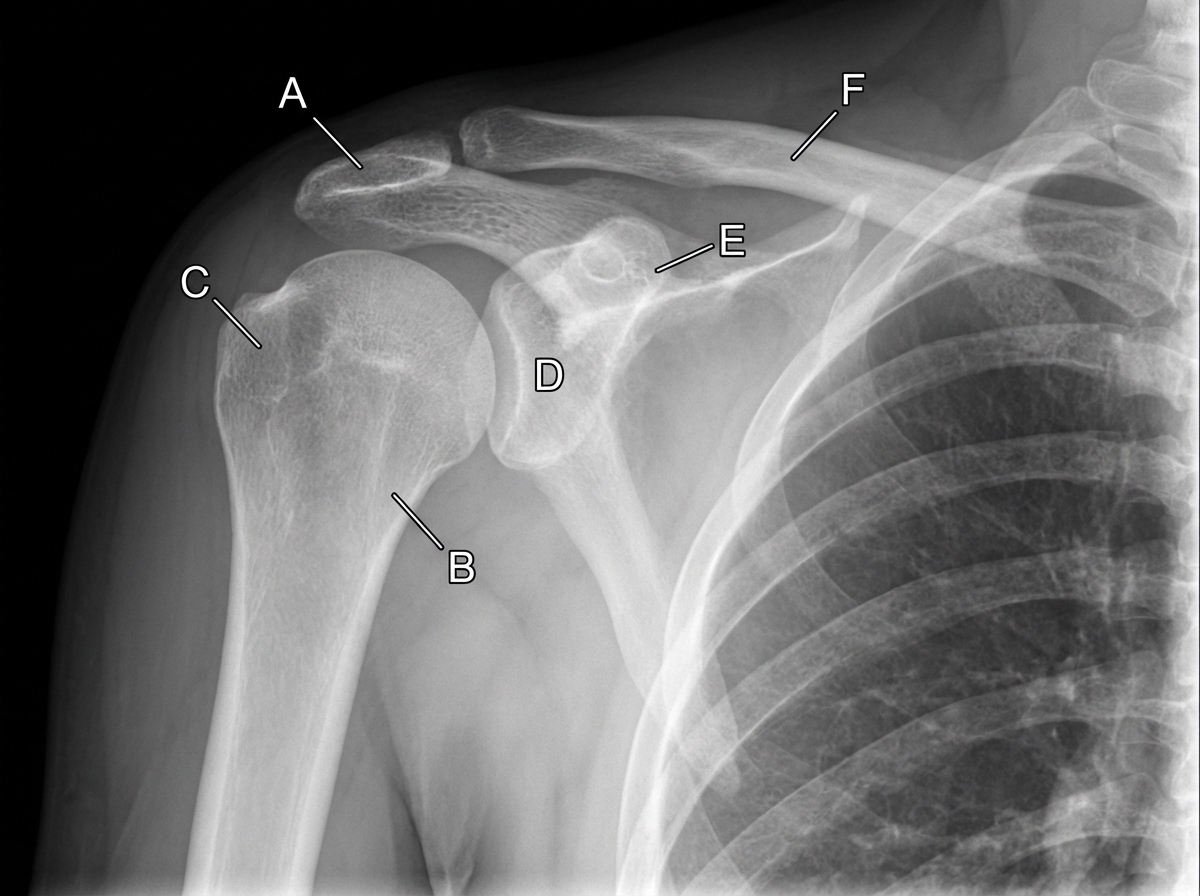

An 11-year-old boy falls down the stairs. A physician examines a radiograph of the boy's shoulder region. If the structure indicated by the letter B is fractured, which of the following structures is most likely injured?

Explanation: ***Posterior humeral circumflex artery*** - The **surgical neck of the humerus** (structure B) is closely related to the **posterior humeral circumflex artery** which courses through the **quadrangular space** with the axillary nerve. - Fractures at this location commonly cause **vascular compromise** and **deltoid muscle denervation** due to injury of both the artery and accompanying axillary nerve. *Musculocutaneous nerve* - This nerve pierces the **coracobrachialis muscle** and runs in the **anterior compartment** of the arm, away from the surgical neck. - It supplies the **biceps, brachialis, and coracobrachialis** muscles and provides sensation to the lateral forearm via the lateral antebrachial cutaneous nerve. *Radial nerve* - The radial nerve travels in the **spiral groove** (radial groove) on the **mid-shaft of the humerus**, not at the surgical neck level. - **Mid-shaft humeral fractures** typically injure the radial nerve, causing **wrist drop** and loss of thumb extension. *Deep brachial artery* - This artery accompanies the **radial nerve** in the **spiral groove** of the humeral shaft, distant from the surgical neck. - It is at risk with **mid-shaft humeral fractures** but not with **surgical neck fractures** as described in this pediatric case.